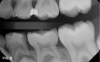

Case 3. This 10-year-old boy was brought to the office for a second opinion regarding restoration of the left primary first molar, which was causing sensitivity (Figure 8). The boy's mother reported that a "tooth-colored filling" had been suggested at another office. The boy was terrified of needle injections and, according to his mother, had required sedation in prior years for restoration of maxillary primary molars. SDF was applied (Figure 9), tooth sensitivity was eliminated, and in 3 months, clinical evaluation and a periapical radiograph confirmed that no other treatment would be needed until the tooth exfoliated (Figure 10 and Figure 11).

Fig 8. 10-year-old patient with distal caries lesion of primary  rst molar. (

Fig 8

Fig 10. 3 months after SDF application, no additional treatment needed.

Fig 10

Fig 11. 3 months after SDF application, no additional treatment needed.

Fig 11